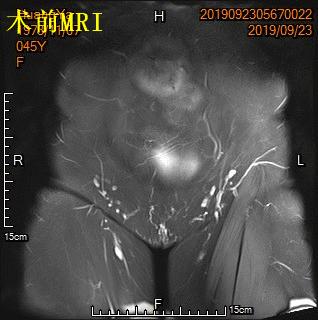

中年女性,发现子宫肌瘤进行性增大5年余。彩超提示多发、巨大子宫肌瘤,肌瘤外突明显,最大者直径近10cm。近半年尿频、尿急症状进行性加重,考虑增大的子宫肌瘤压迫膀胱所致。

- 盆腔磁共振检查显示显示多发巨大子宫肌瘤,部分突出浆膜外,明显压迫膀胱。

MRI显示多发子巨大宫肌瘤,压迫膀胱

冠状位